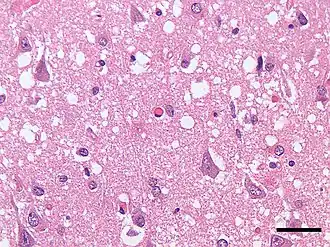

- морфологическое и гистологическое исследование тканей головного мозга (коры, подкорковых ядер) при аутопсии (посмертная диагностика).